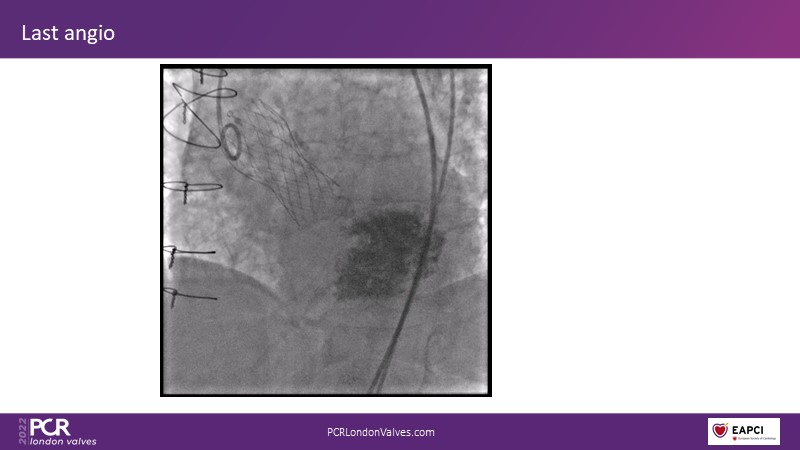

This session reflects on the importance of device choice and implantation technique in complex TAVI procedures. Learn how to anticipate the risks of a valve-in-valve procedure in small surgical prostheses, and discover the latest technological evolutions for treating patients with complex anatomy.

- To appreciate the importance of device choice and implantation technique in complex TAVI procedures

- To learn how to anticipate the risks of a valve-in-valve procedure in small surgical prostheses